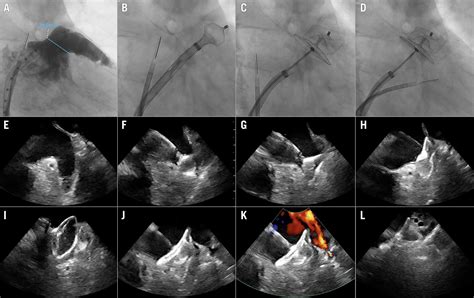

During the procedure, an interventional cardiologist or electrophysiologist guides a catheter through a vein in the groin, up to the heart. They then deploy a specialized device—often a parachute-shaped or plug-like implant—that fits securely into the opening of the LAA. Over time, the body’s natural tissue grows over the device, effectively creating a permanent seal.

1. Pre-procedural Imaging: Using a Transesophageal Echocardiogram (TEE) to visualize the LAA and ensure it is free of existing clots.

3. Catheter Placement: The physician gains access through the femoral vein and crosses the septum to reach the left atrium.

4. Deployment: The occlusion device is deployed to perfectly fit the dimensions of your LAA.

5. Observation: Once the device is confirmed to be stable and sealing the area correctly, the catheters are removed.